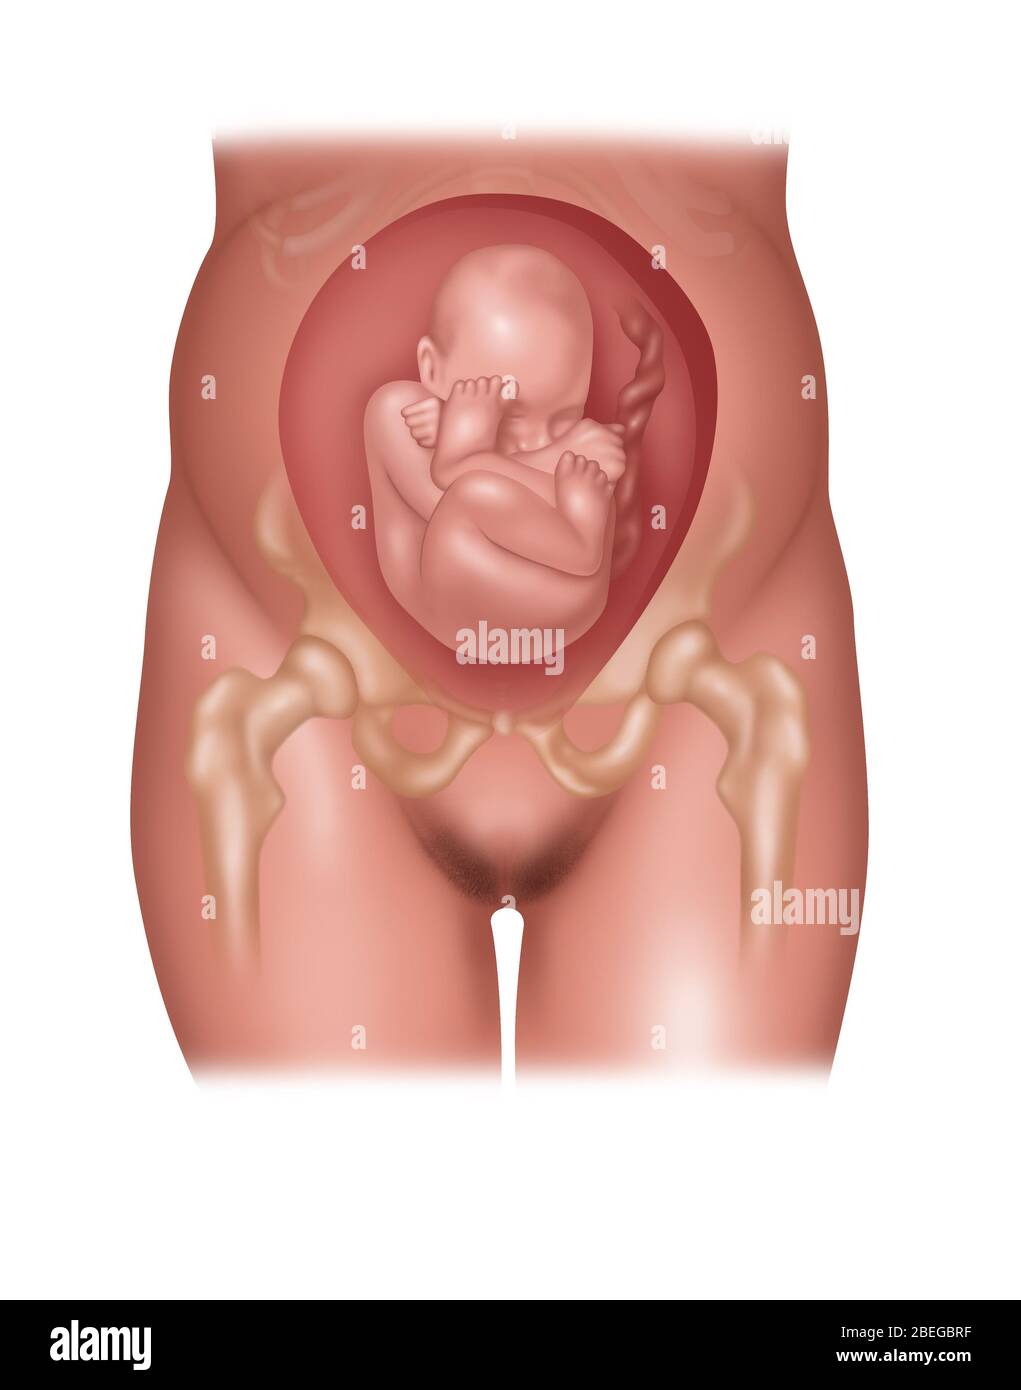

Fetus Positions in Uterus, Illustration Stock Photohttps://www.alamy.com/image-license-details/?v=1https://www.alamy.com/fetus-positions-in-uterus-illustration-image353173031.html

Fetus Positions in Uterus, Illustration Stock Photohttps://www.alamy.com/image-license-details/?v=1https://www.alamy.com/fetus-positions-in-uterus-illustration-image353173031.htmlRF2BEGBPF–Fetus Positions in Uterus, Illustration